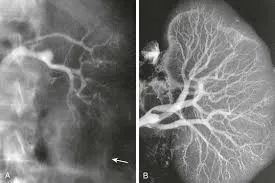

Injúria Renal Aguda (revisão Lancet 2025)

Injúria Renal Aguda (revisão Lancet 2025)